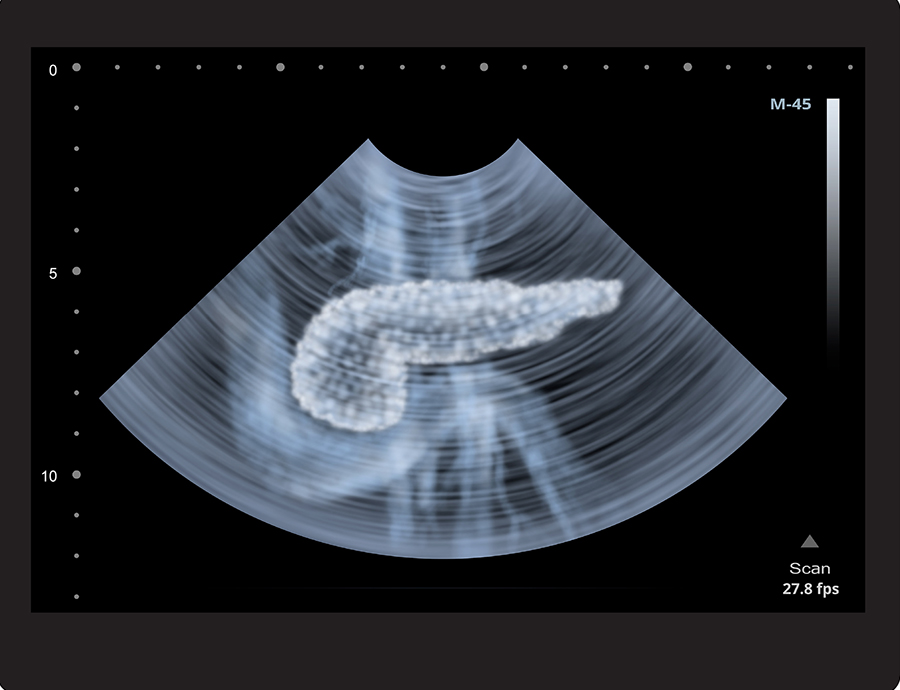

Understanding Pancreatitis - The Lesser Known Digestive System Disease

the digestive system includes many organs working in harmony to maintain health. Every organ is integral for optimal body function, but there are some organs which are less known than others. One such less known organ is the pancreas.

The word pancreas is derived from the Greek word pánkreas (pán = all, and kreas = flesh). The organ itself is located horizontally in the upper abdomen, deep beneath the stomach. Historically, it was believed to be a cushion for the stomach! However, it is now clear that the pancreas has two essential functions: the production of digestive enzymes and the regulation of sugar balance.

Like all body organs, the pancreas can become diseased, and one disease that can affect the pancreas is pancreatitis. Pancreatitis essentially means “swelling or inflammation of the pancreas.” Pancreatitis can be either sudden (acute) or slowly progressive (chronic). Each of these two disorders has unique features.